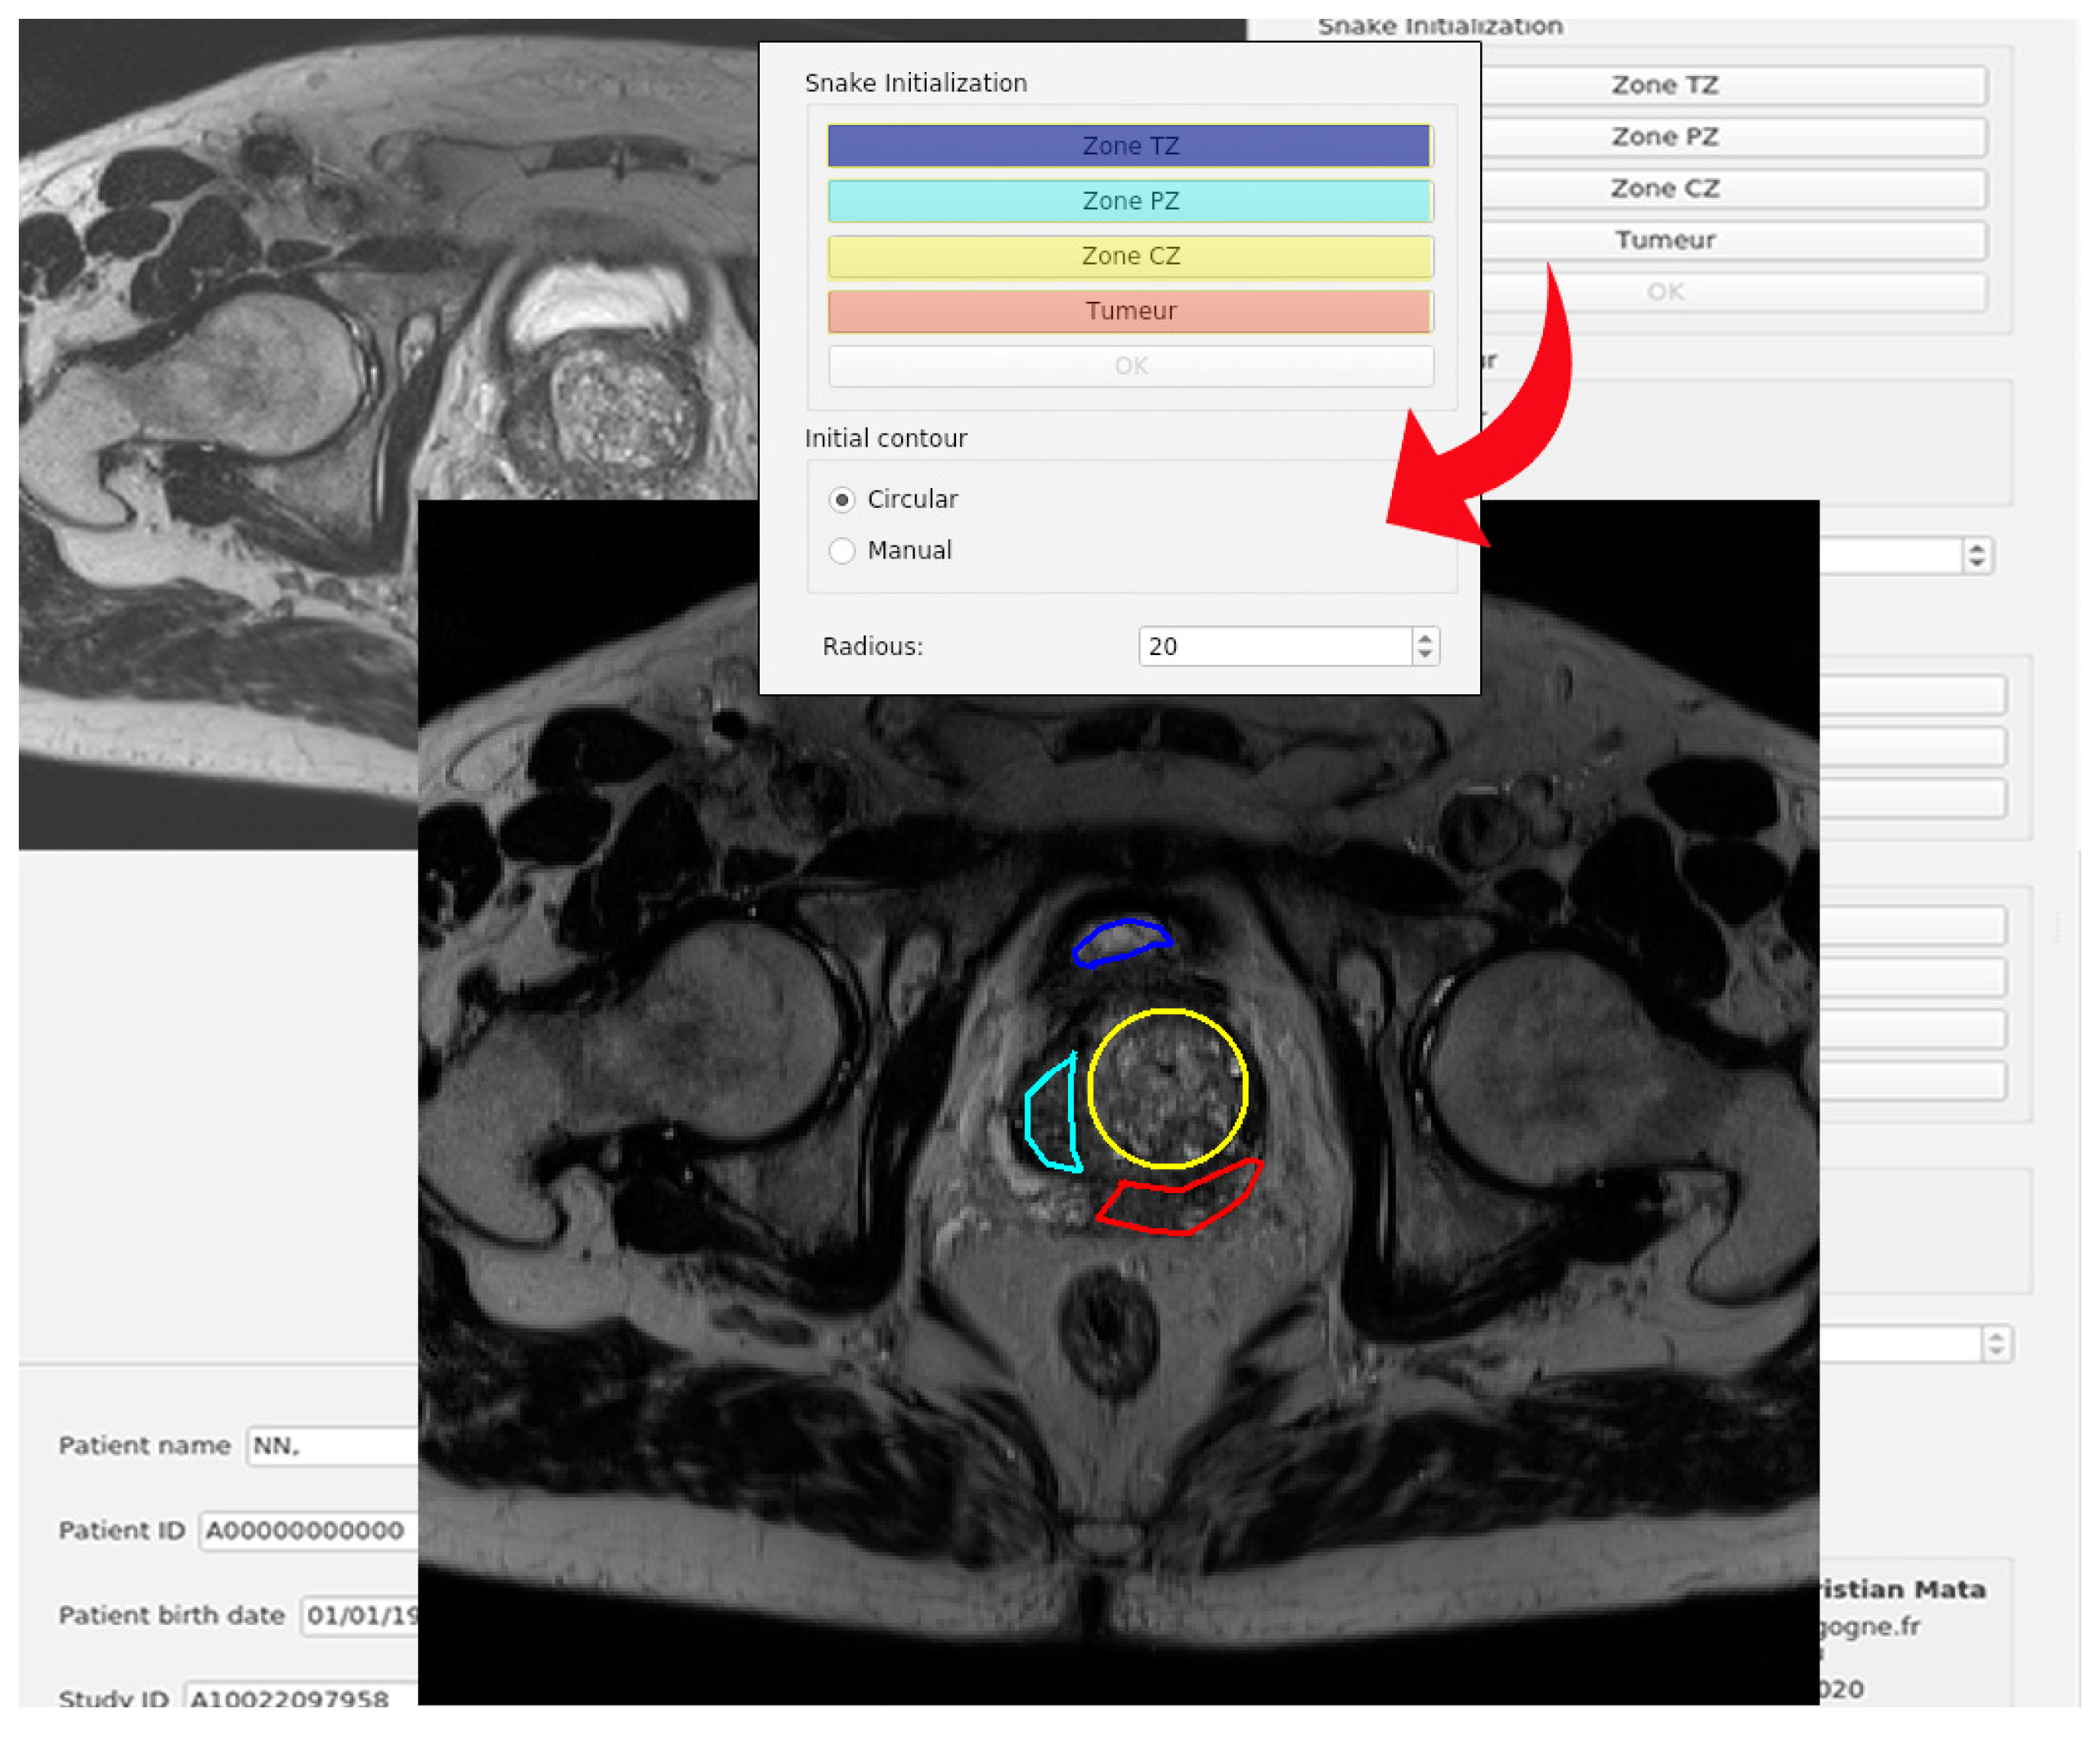

In this section, the code organization and the user interface of the program will be explained. The main window of the program is shown in Figure 3. All the code has been developed in Python, using the modules PyQt for the user interface and PyDicom to open the files included in the testing dataset. The code has been organized in modules that do not interact with each other. The integration of all of them has been made in the Main Window class.

The data available to the user includes the images and the patient data fields. This module is also in charge of anonymizing the files and writing them into disc. The functionalities of this module can be accessed through the buttons in the Section 1 of the Figure 3.

• Image segmentation. This module stores all the Python code related to the segmentation procedure. The main class in this module is Segmentation-Hub, which is in charge of selecting the right class for the object that will produce the segmentation, according to the method chosen by the user. The selection of the segmentation method can be done in Section 2 of Figure 3. By implementing the methods in this manner, the actual implementation of the segmentation task is completely transparent for other classes that make use of this module. To select certain segmentation method, only a label that defines the method must be provided.

• Image widget. This module is in charge of showing the image, as well as the initial and the resulting contours from the segmentation. The same module is used for both, left and right images. It also captures the clicks from the user to generate either the circular or the manual initial contour. Both types of initialization will be explained later. The image widget is represented in Sections 3 and 4 of Figure 3.

• Model 3D widget. It shows a 3D representation of the output segmentation, based on the Python module Matplotlib. This process is relatively simple as it only replicates the given contour vertically. If the spatial resolution is given in the input DICOM file, the scale of the axis will be given in millimeters. It can be accessed through the button S h o w 3 D M o d e l located in Section 5 of Figure 3.

• Snake init widget. This widget is in charge of handling all the functionalities of the Snake initialization group, placed at the top of the central control panel of the application.

Each button will request the main window to ask the user to enter the initial contour in the left image. Once the user has finished, the gathered contours are returned back to this module.

Afterwards, the corresponding masks for those contours can be generated for the snake algorithm (the mask consists of an image with values of 1 in the interior of the contour, and zeros outside of it). The interface for this module is represented in Section 6 of Figure 3.

• User data widget. It is implemented as an efficient and easy to use manner to handle all the user information as an object, and to show it. This class stores all the information related to the patient or the study, retrieved from the DICOM file. It also contains the corresponding widgets that are shown below the left image area, where the gathered information is displayed (see Section 7 of Figure 3).

Finally, regarding the user interface showed in Figure 3, this program has four well-defined sections:

• Left panel. In this area (highlighted in blue), the loaded images are shown, and the user can draw the initial contours of the snake of the different areas of the prostate. Each prostate zone is surrounded with a different color to make it easily distinguishable (see Figure 3)

• Right panel. This area (highlighted in orange) shows the loaded images, and the results of the evolution of the selected snake algorithm. Each prostate zone has a pre-defined color, and they match with the colors used for the initial contours (see Section 4 of Figure 3).

• Bottom area. The patient information retrieved from the DICOM file is shown (highlighted in blue). Moreover, information related to the spatial resolution and thickness of the gathered slice are included (Section 7 of Figure 3)

• Central area. This is the control panel area (highlighted in green). All the functionalities and possible configurations of the program are located in this area. It is represented in the Sections 1, 2, 5 and 6 of Figure 3.

Figure 3. GUI interface of the developed active contour segmentation tool using a prostate MR image.